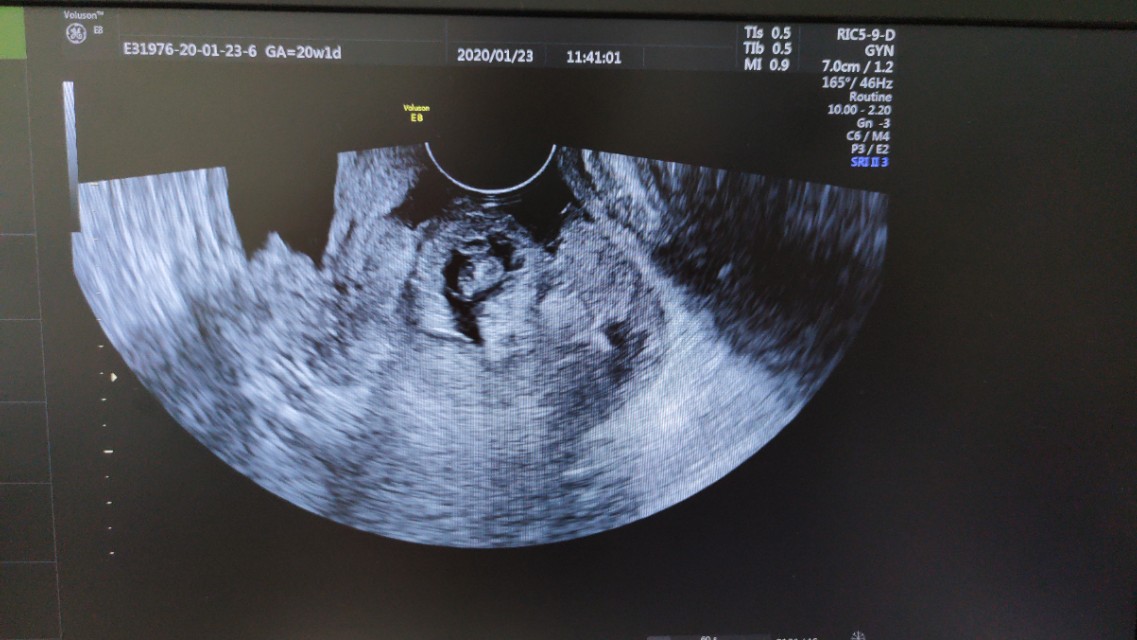

紧急将患者推往妇产科B超室,行阴式超声检查示:宫颈前唇膨大,内见孕囊,提示宫颈妊娠,见心管搏动。阴道内见大量凝血块,大量鲜血流出。

妇产科医生精确诊断为--异位妊娠:宫颈妊娠,失血性休克,立即启动应急预案,建立静脉通路、输血、实施阴式取胚术。